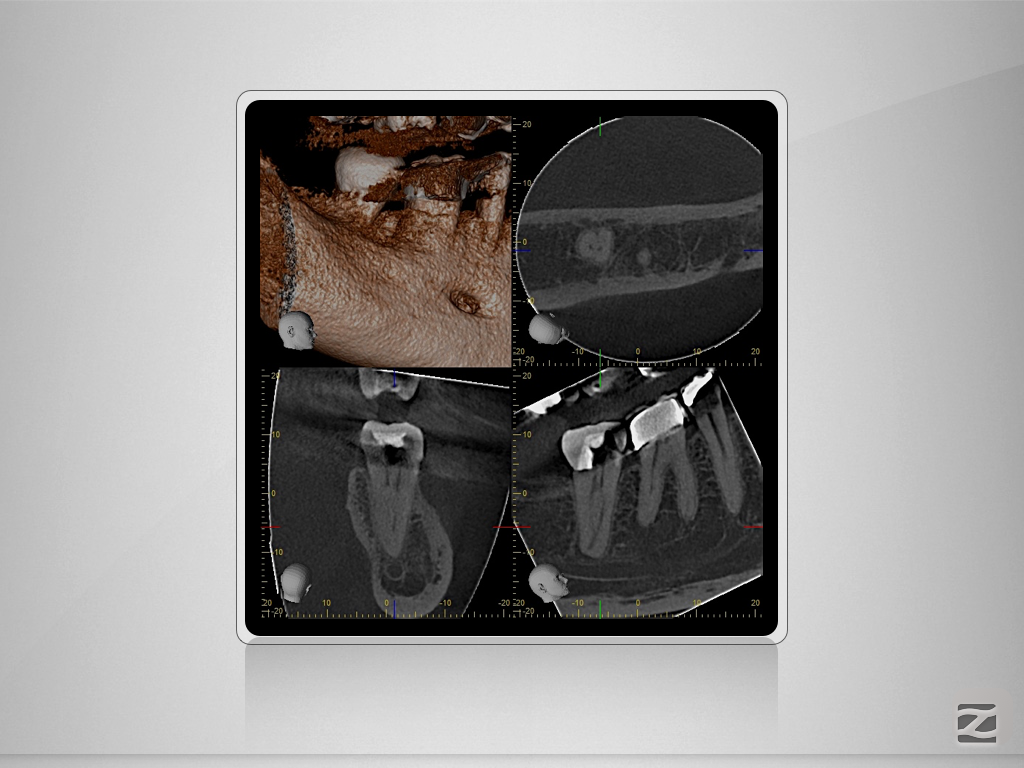

47d-006

„C“ ja – „C“ nein